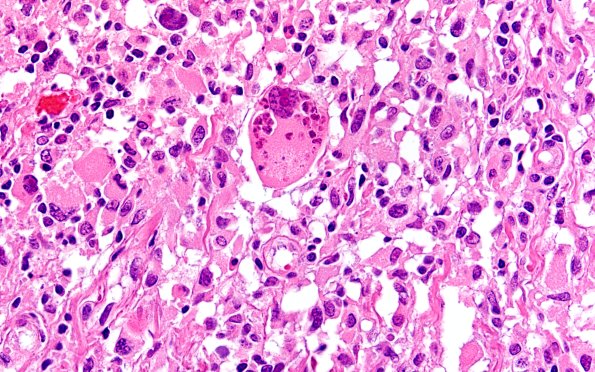

22B18 PXA (Case 22) H&E 60X 5

Some tumor cells have numerous nuclei which vary in size. (H&E)